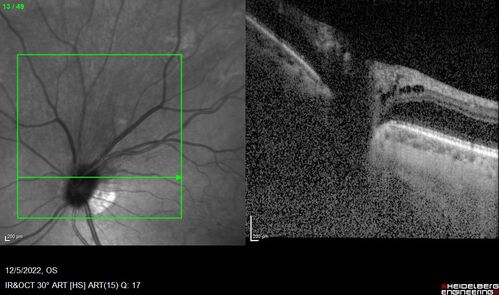

Macular schisis with no leakage on FA - Presumed Nerve pit maculopathy

73-year old female. Had treatment trial with Eylea with no benefit (4 months). Vision is 20/32 in left eye and has remained there (with a dense cataract).